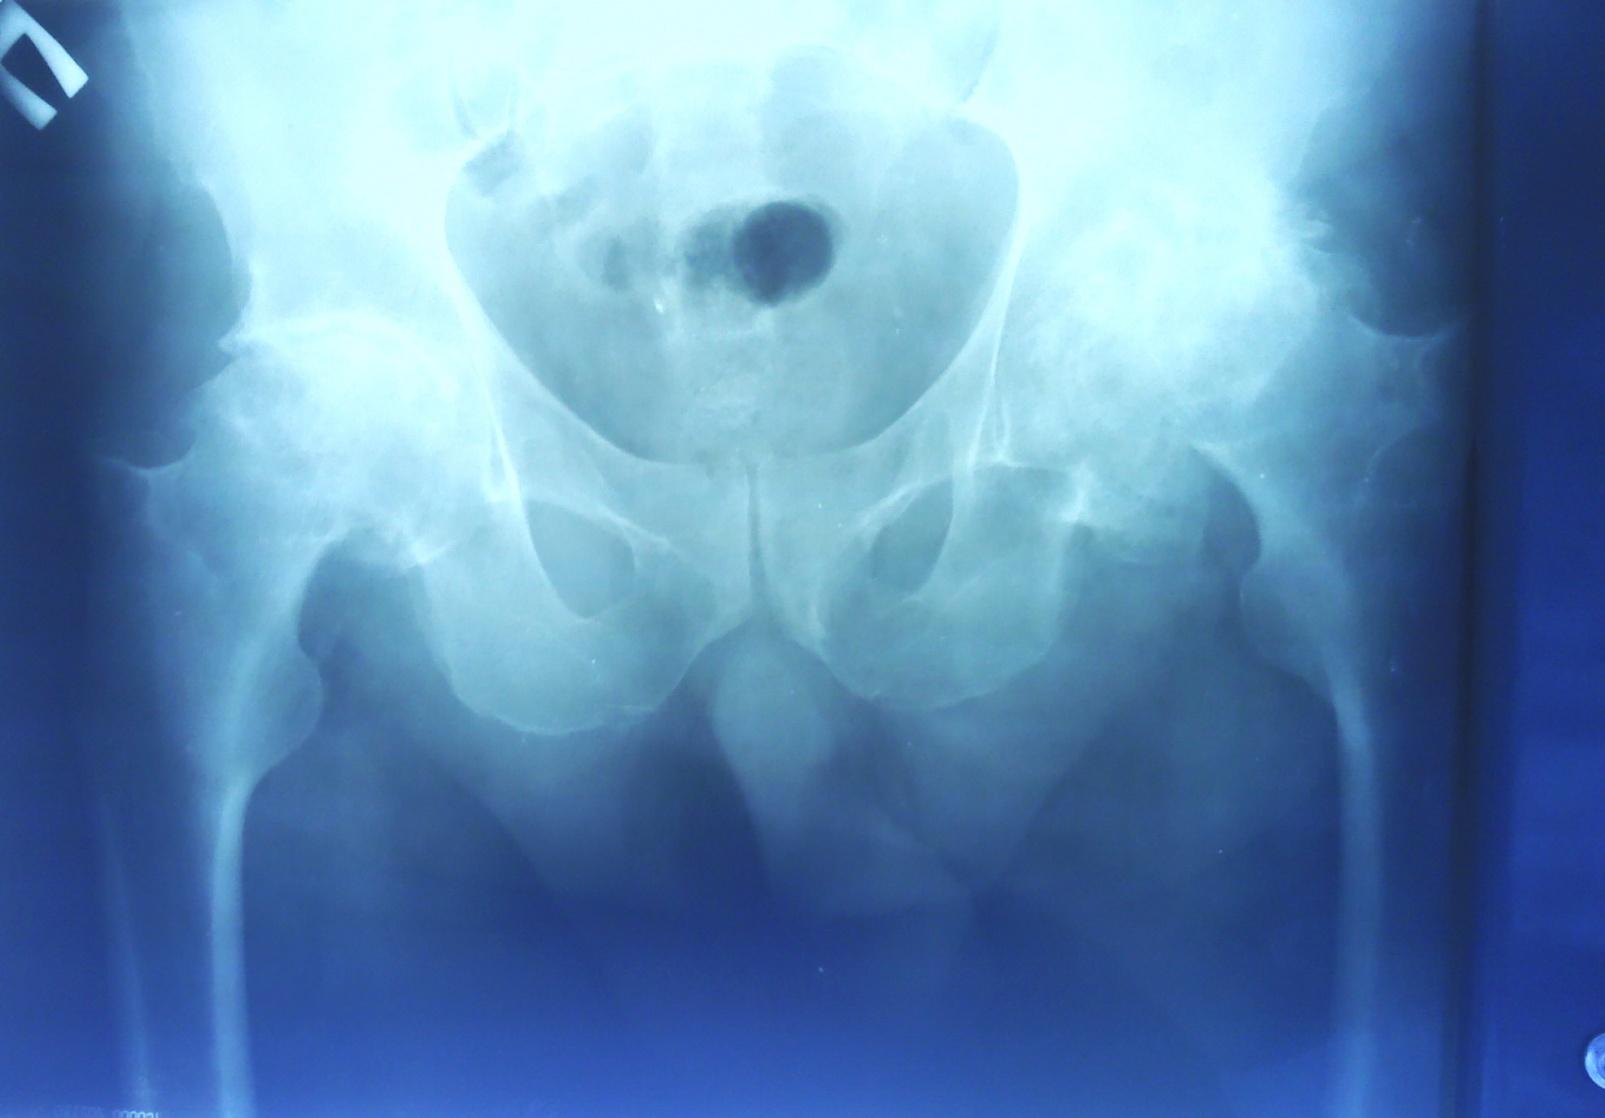

7.Rtg костей таза от 22.03.13г:

Правый тазобедренный сустав: Субхондральный склероз вертлужной впадины. Костные разрастания по верхнему и нижнему краю вертлужной впадины. Сужение суставной щели. Умеренная грибовидная деформация головки бедренной кости с кистовидными изменениями.

Левый тазобедренный сустав: определяется резкое сужение суставной щели. Деформация головки бедренной кости с кистовидными изменениями и присоединением остеопороза. Вертлужная впадина умеренно деформирована с краевыми костными разрастаниями и кистовидными изменениями.

Заключение: Признаки коксартроза правого правого тазобедренного сустава III ст., коксартроз левого тазобедренного сустава III ст.

На основании жалоб больного (на боли в области тазобедренных суставов, ограничение движений в них), анамнеза заболевания (считает себя больным в течение 10-ти лет, когда впервые появились боли при ходьбе в тазобедренных суставах. Постепенно боли усиливались, появились ограничения подвижности в тазобедренных суставах), данных локального статуса (Нижние конечности не отёчны. Движения в тазобедренных суставах ограничены, болезненны. Пальцы стоп теплые, движение и чувствительность сохранены. Стояние и ходьба с помощью опоры (костылей). Тонус мышц сохранен.), инструментальных исследований (На рентгенограмме тазобедренных суставов от 22.03.13: Признаки коксартроза правого правого тазобедренного сустава II ст., коксартроз левого тазобедренного сустава III ст.) можно поставить клинический диагноз: Двухсторонний коксартроз III ст.